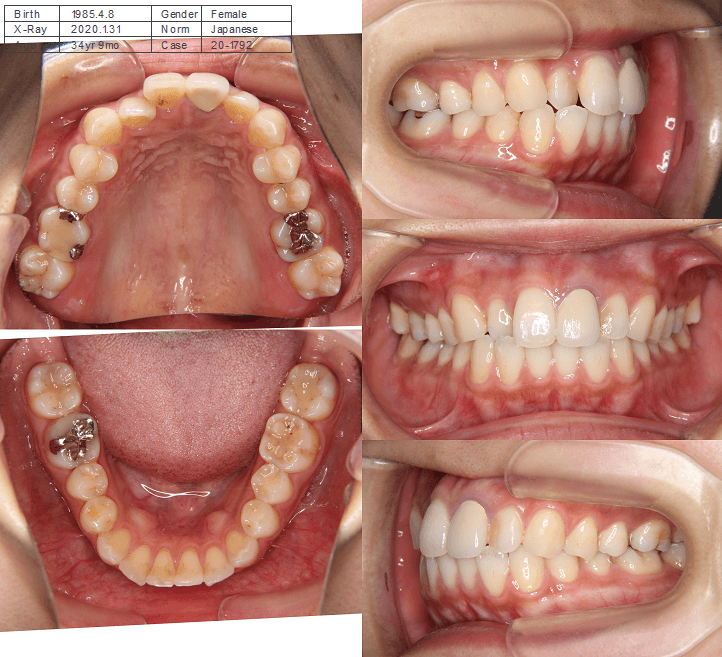

| 年齢・性別 | 34歳の女性 |

|---|---|

| 主訴 | 口元の突出感が気になり、将来的な咬合状態を整える目的で来院された患者様です。 |

| 治療期間・回数 | 3年3ヶ月・31回 |

| 費用 | 830,000円 |